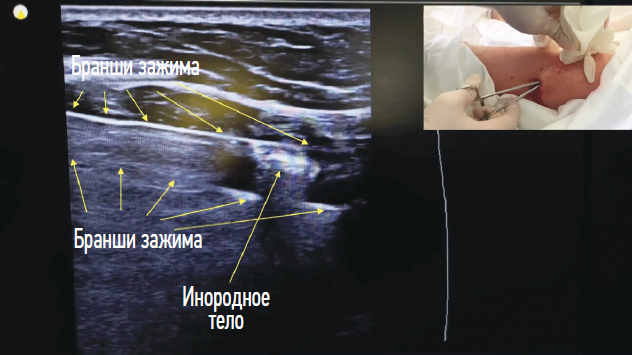

Во II группе у всех пациентов оперативное вмешательство выполнялось под местной анестезией. При этом в операции участвовал только один хирург вместе с операционной сестрой. После УЗ визуализации ИТ в МТ (рис. 6) его удаляли одним из двух способов. Первый способ — через раневой канал, второй — через отдельный минимальный разрез по кратчайшей траектории. Второй способ использовали, когда ИТ находилось на достаточно большом расстоянии от входного отверстия раневого канала на кожном покрове (рис. 7). При этом размеры операционного дополнительного доступа, как правило, были сопоставимы с диаметром извлекаемого ИТ и варьировали от 5 до 15 мм (M ± m 8,2 ± 1,4 мм) (рис. 8). В процессе оперативного вмешательства удавалось убрать все визуализируемые осколки. Как правило, во время операции удаляли 3–4 осколка (максимально — до 10). Время оперативного вмешательства во II группе колебалось от 3 до 35 мин (M ± m 18,5 ± 4,3 мин).

Рис. 7. Ультразвуковая визуализация браншей зажима с инородным телом

Fig. 7. Ultrasonic visualization of the clamp branches with a foreign body